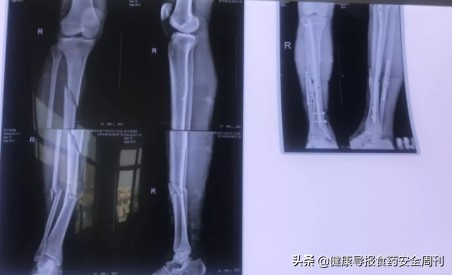

据祈康综合外科主任王宏亮介绍,通过完善相关检查,从X光片上可以看到,陈师傅右下肢从膝盖到脚踝多处断裂,决定为患者进行骨折切开复位术,用手术方法显露骨折部位,施行骨折端的修正和复位;并根据骨折的不同情况,选用各种内固定物,保持复位后的位置,一般骨折切开复位后,多同时行内固定术。

患者骨折手术前后对比